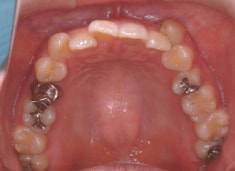

治療前

治療後(2年5ヶ月後)